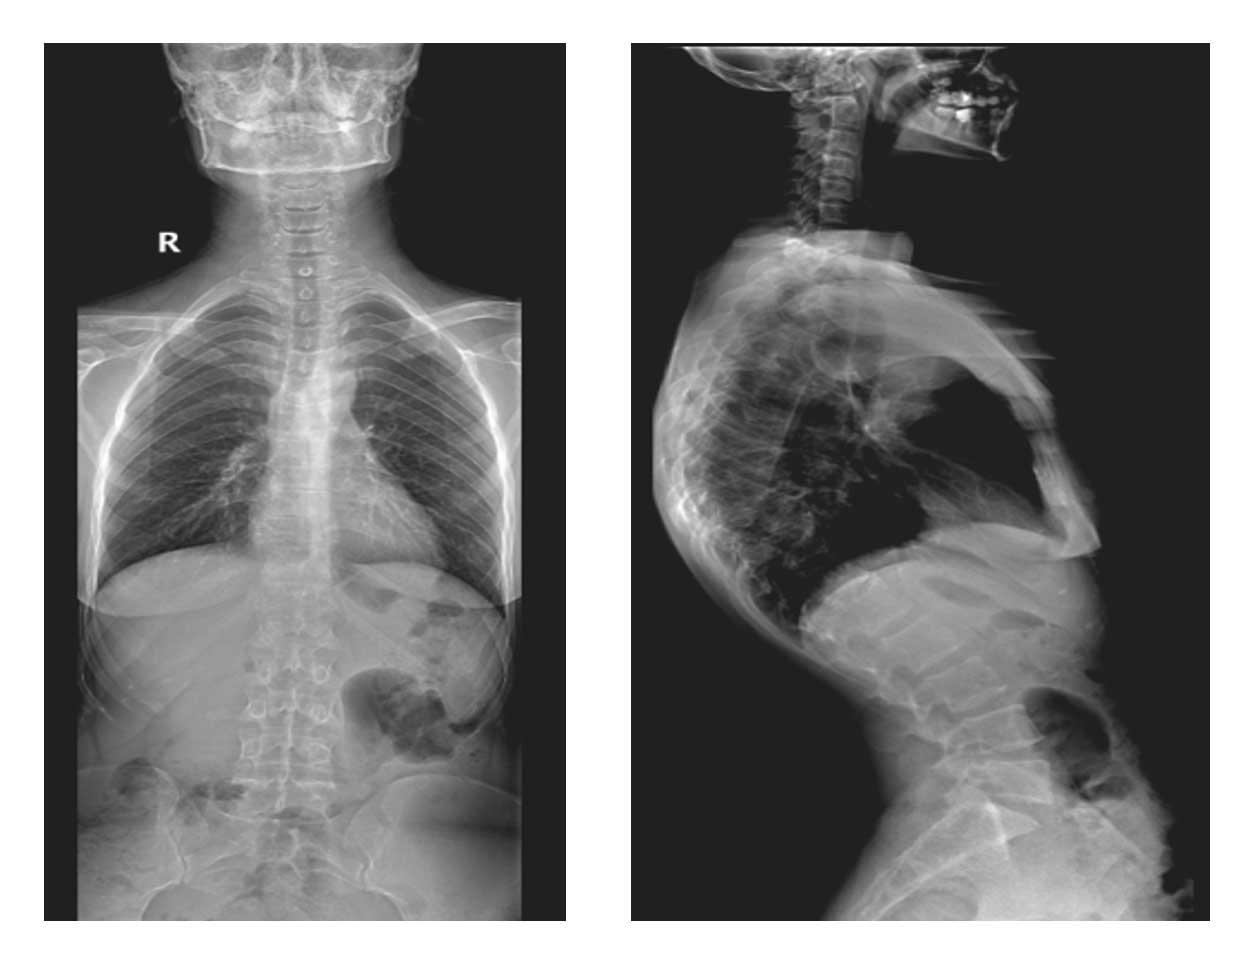

Ameliyat Öncesi: Röntgende L3 vertebrada litik lezyon görülmekte.